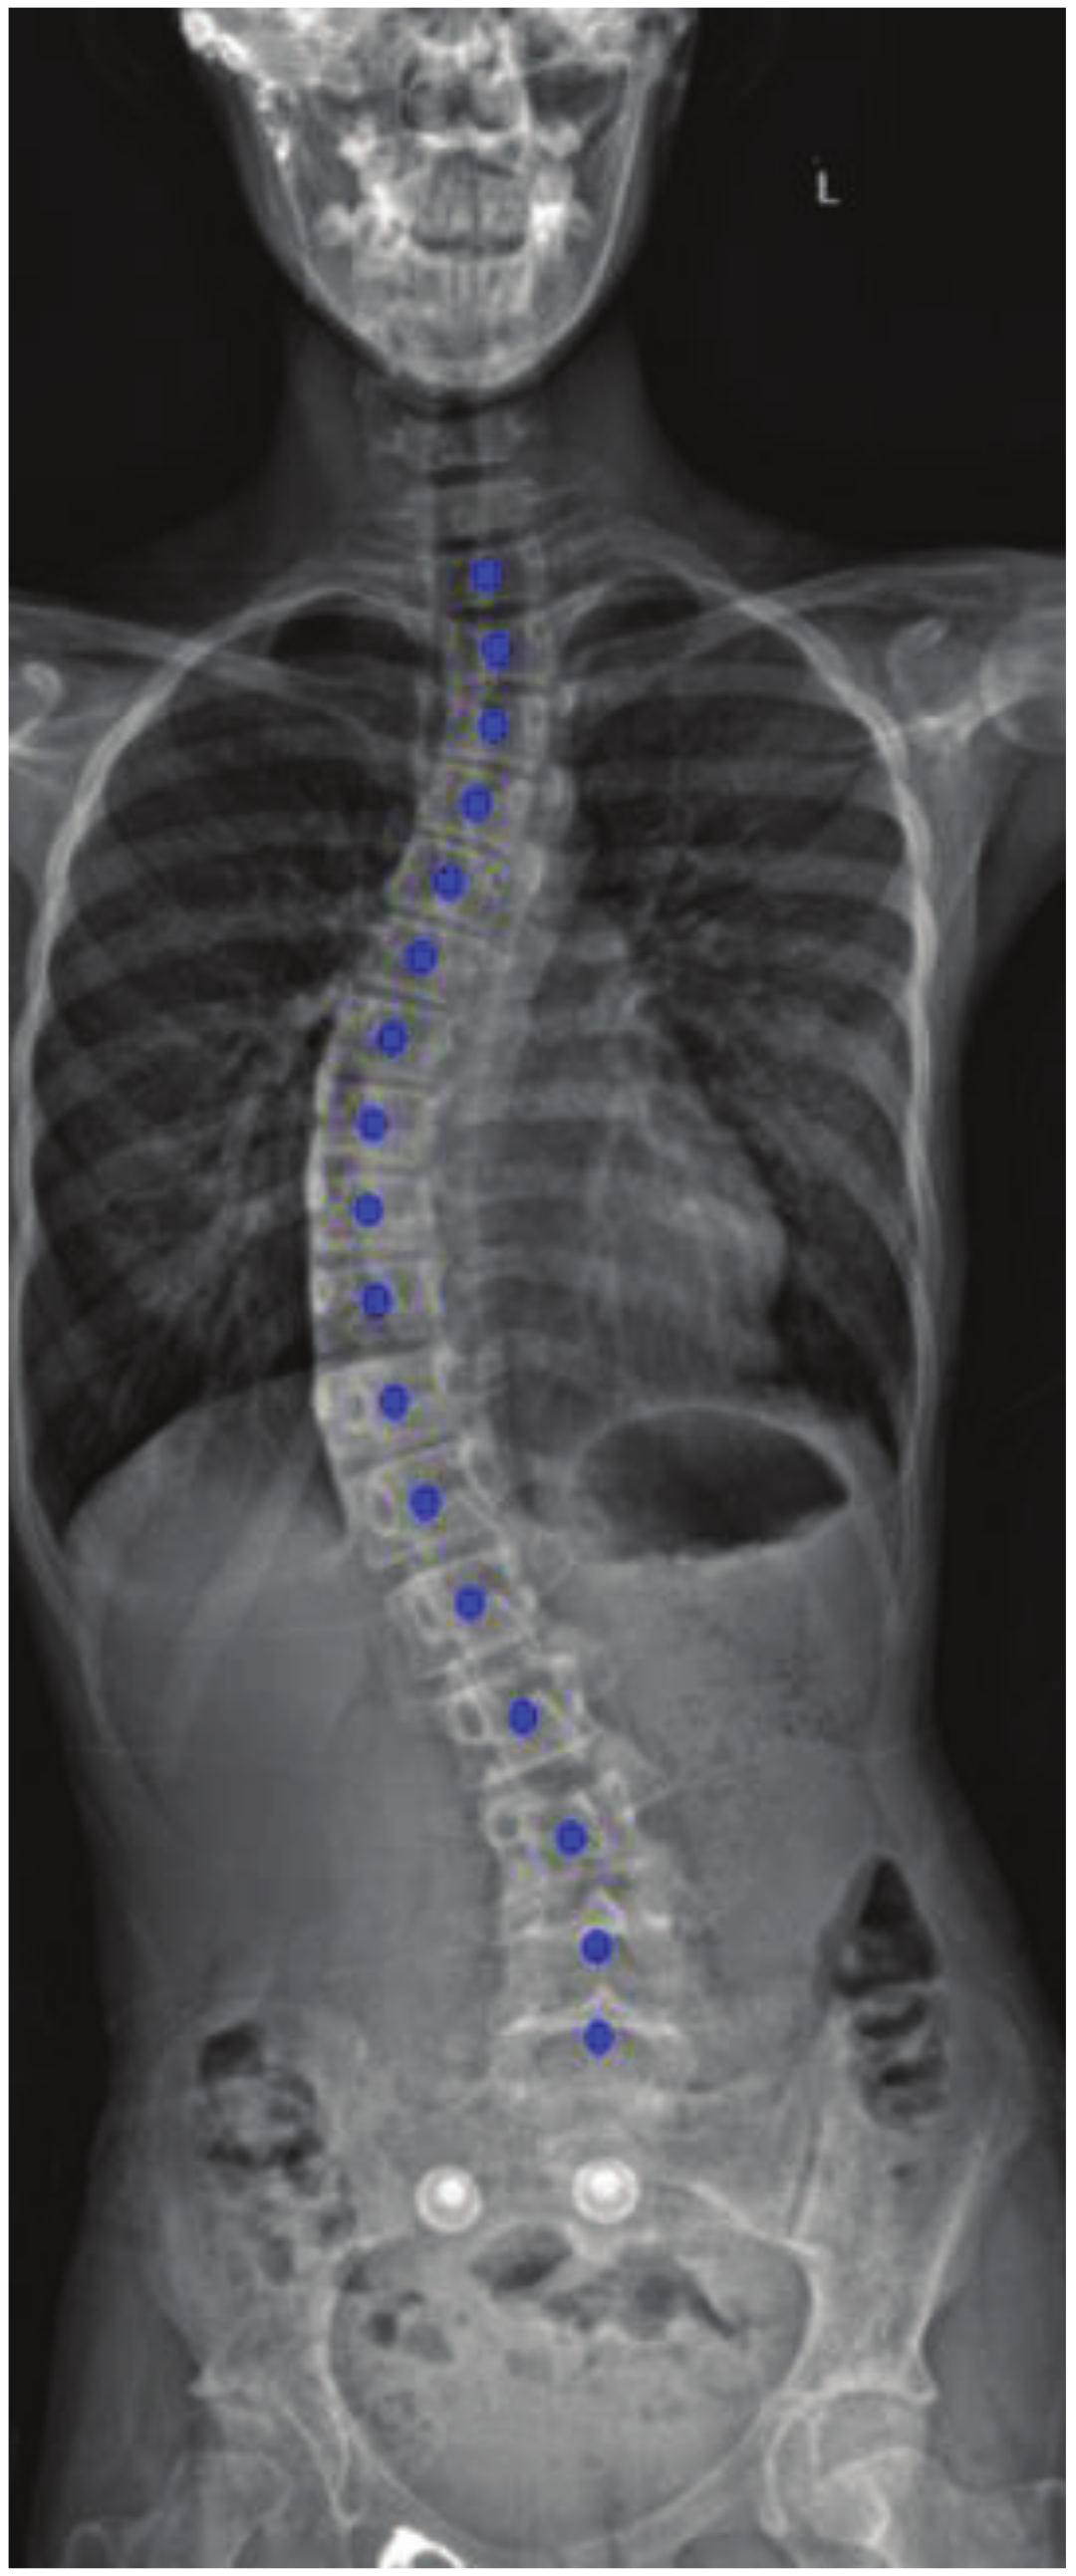

4. Results